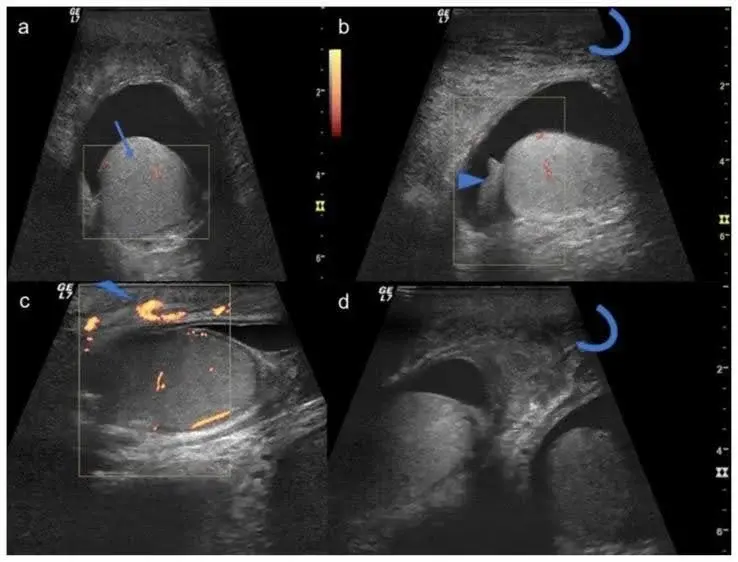

Diagnostic imaging is essential to confirm the cause of scrotal swelling and urinary dysfunction. Ultrasound is the first-line imaging tool to distinguish between hydrocele, varicocele, infection, tumors, or fluid accumulation. In cases of urinary retention or more complex findings, a CT scan of the abdomen and pelvis provides a clearer picture—showing conditions like hydronephrosis, cystocele, or urethral dilation, as seen in the case where penile and scrotal edema was linked to mechanical obstruction.

Post-void residual (PVR) volume measurement helps evaluate how well the bladder is emptying. In one study, patients with scrotal edema and urinary retention had measurable post-void volumes and visible bladder distension.